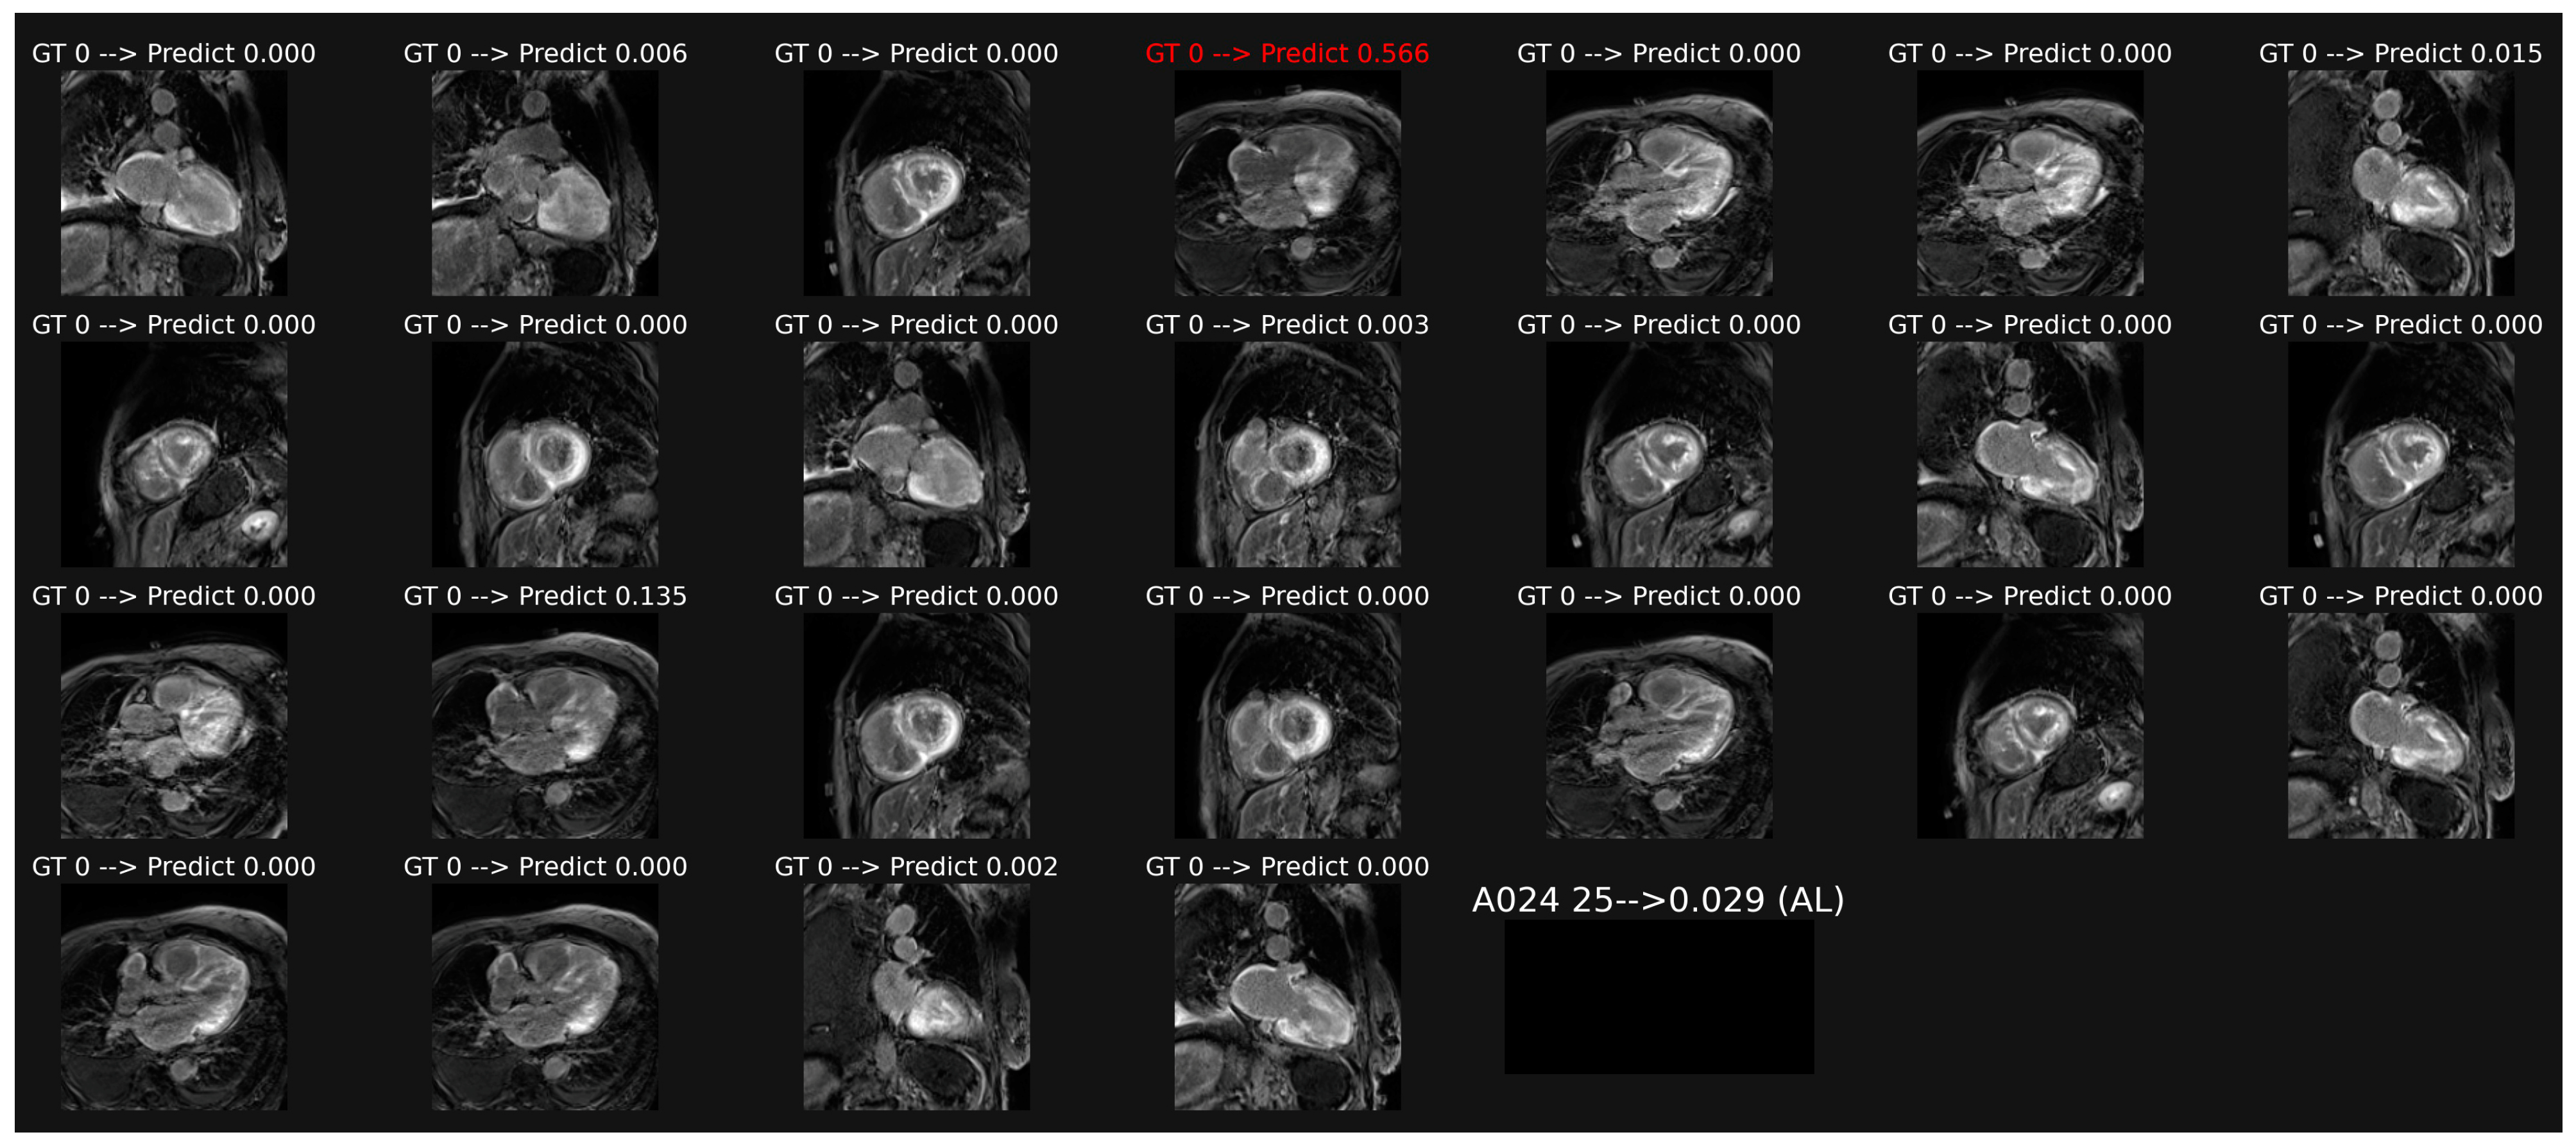

3.1. Classification of Cine-MR Images

3.2. Classification of LGE Images